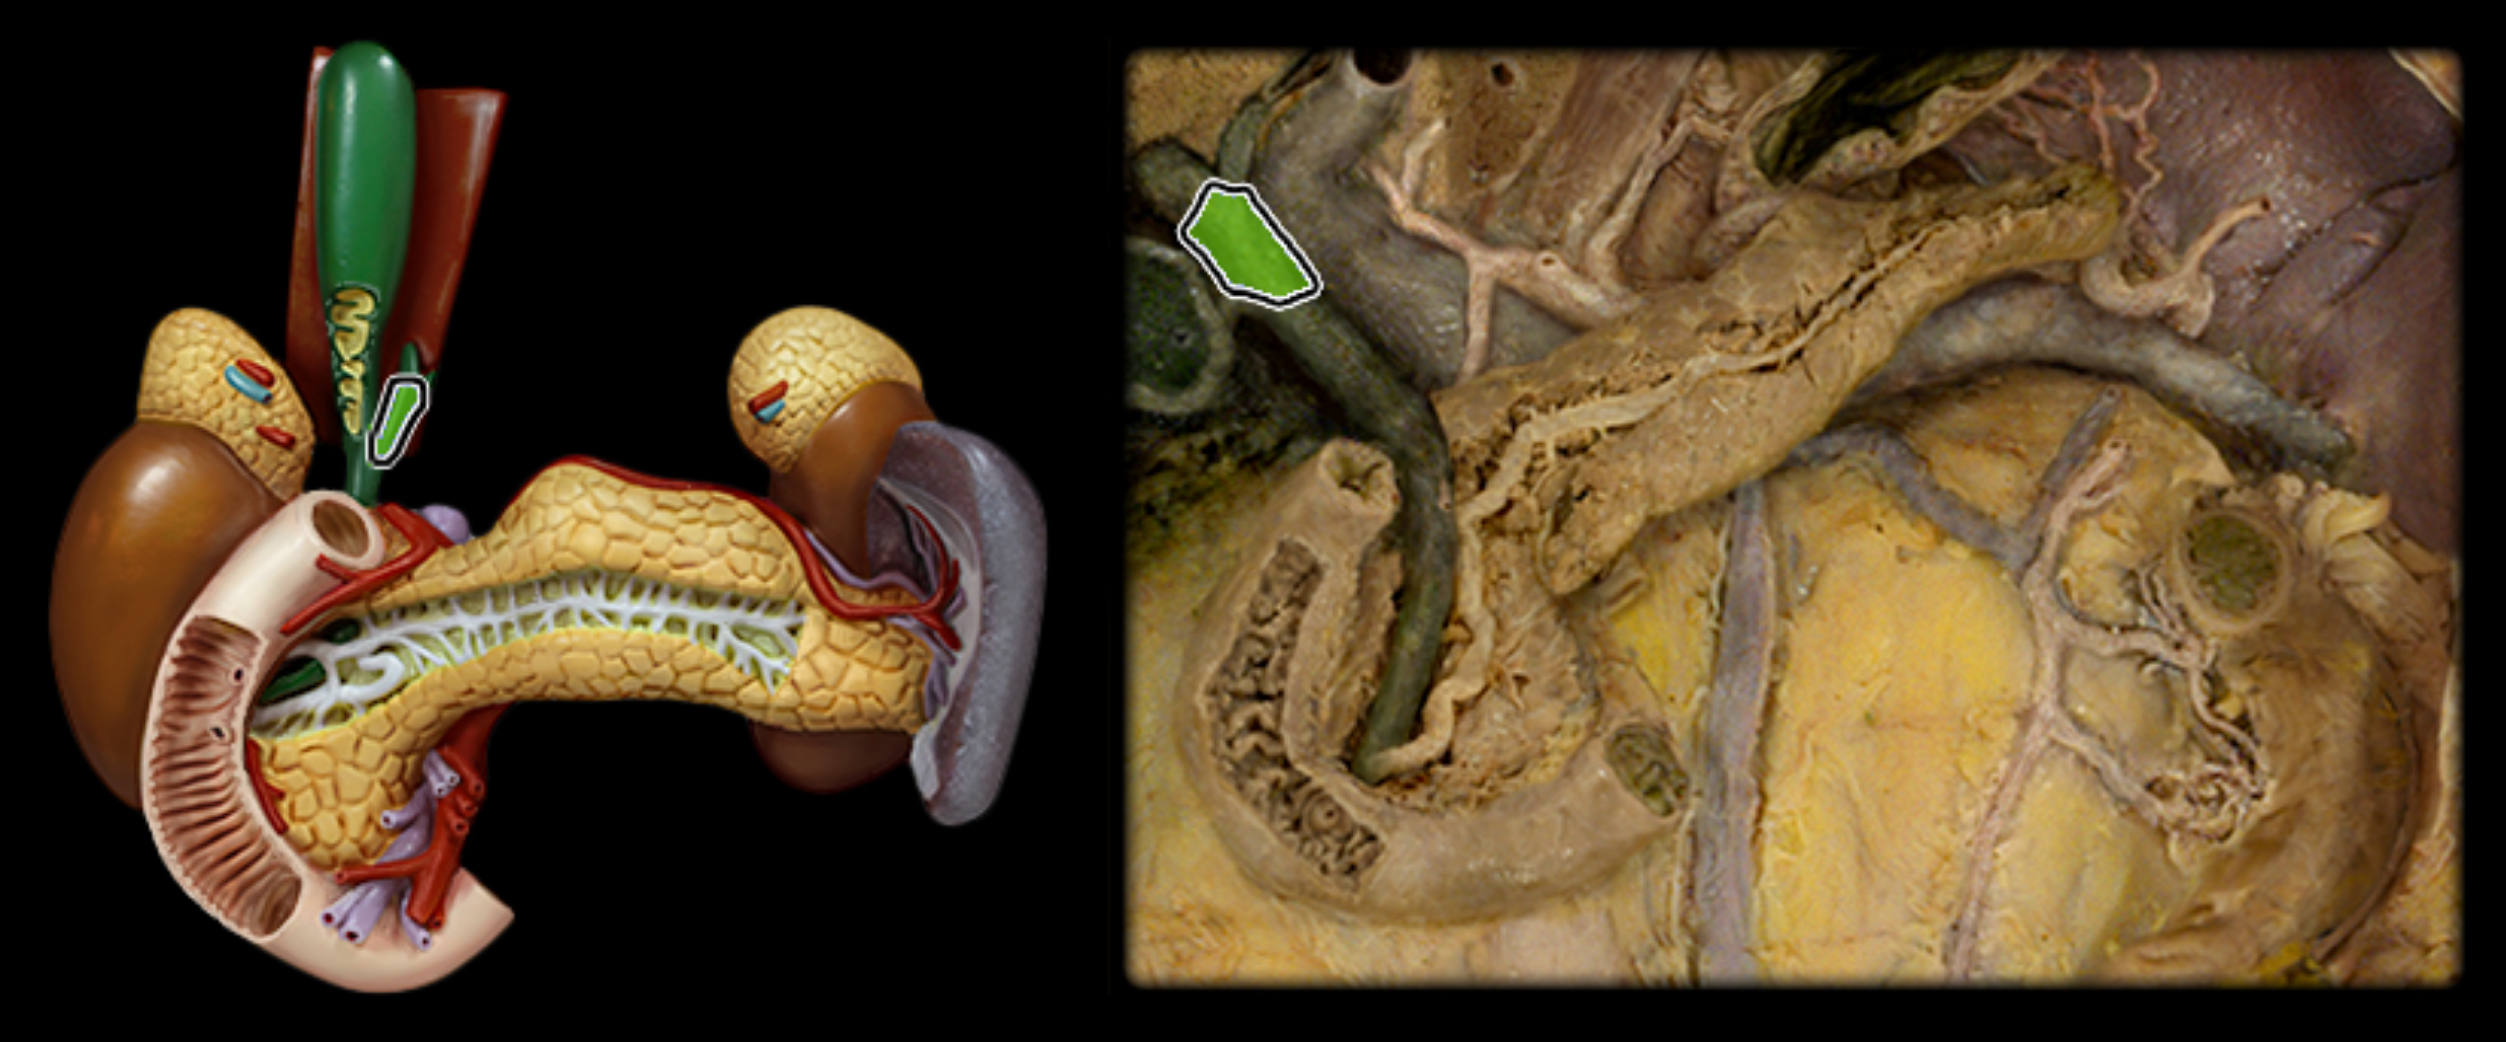

Hepatic ducts (you do not need to distinguish R/L)

Common hepatic duct

Cystic duct